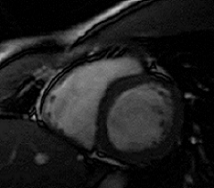

Our research brings physics and mathematics tools to the study of biological systems ranging from understanding the biomechanics of cardiovascular and cerebrovascular diseases to modeling physiological systems. Our ultimate goal in each research initiative is to use mathematical and engineering principles to establish new techniques and/or devices that are relevant for practicing clinicians. We use clinical, experimental, and computational methods to investigate our hypothesis